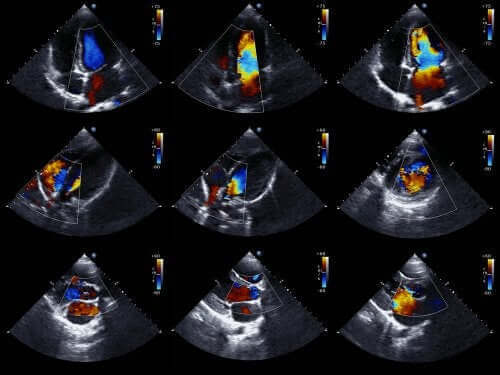

Ехокардиограмите са едни от най-успешните техники за диагностициране на вродени сърдечни проблеми.

Лекарите обикновено могат да диагностицират тази аномалия още преди да се роди бебето. За да направят това, те използват ехокардиограма за новородени. Това е техника, която използва звукови вълни, за да създаде движещ се образ на сърцето.

Благодарение на това, можем да видим външния вид на сърцето и да прегледаме неговата функция, когато бебето е все още в утробата. С тази информация, лекарите могат да предпишат лечение веднага след раждането.